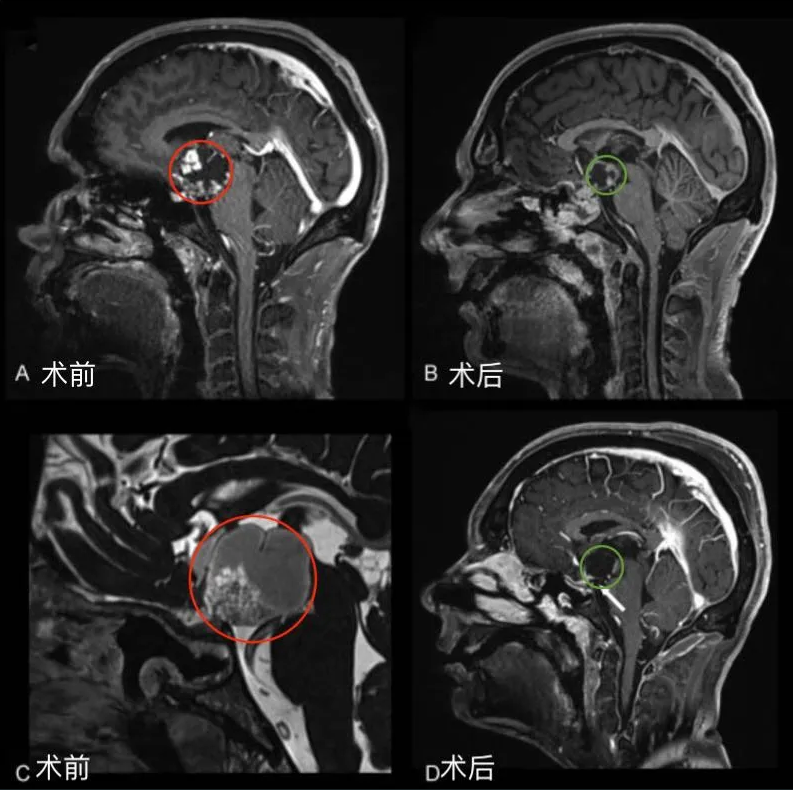

图1后视交叉性巨大颅咽管瘤患者肿瘤术前(A,C)和术后(B,D)矢状位增强MR对比,显示肿瘤全切。

术后情况

视力、视野恢复正常,没有颅神经麻痹症状,认知功能改善,垂体功能恢复正常。